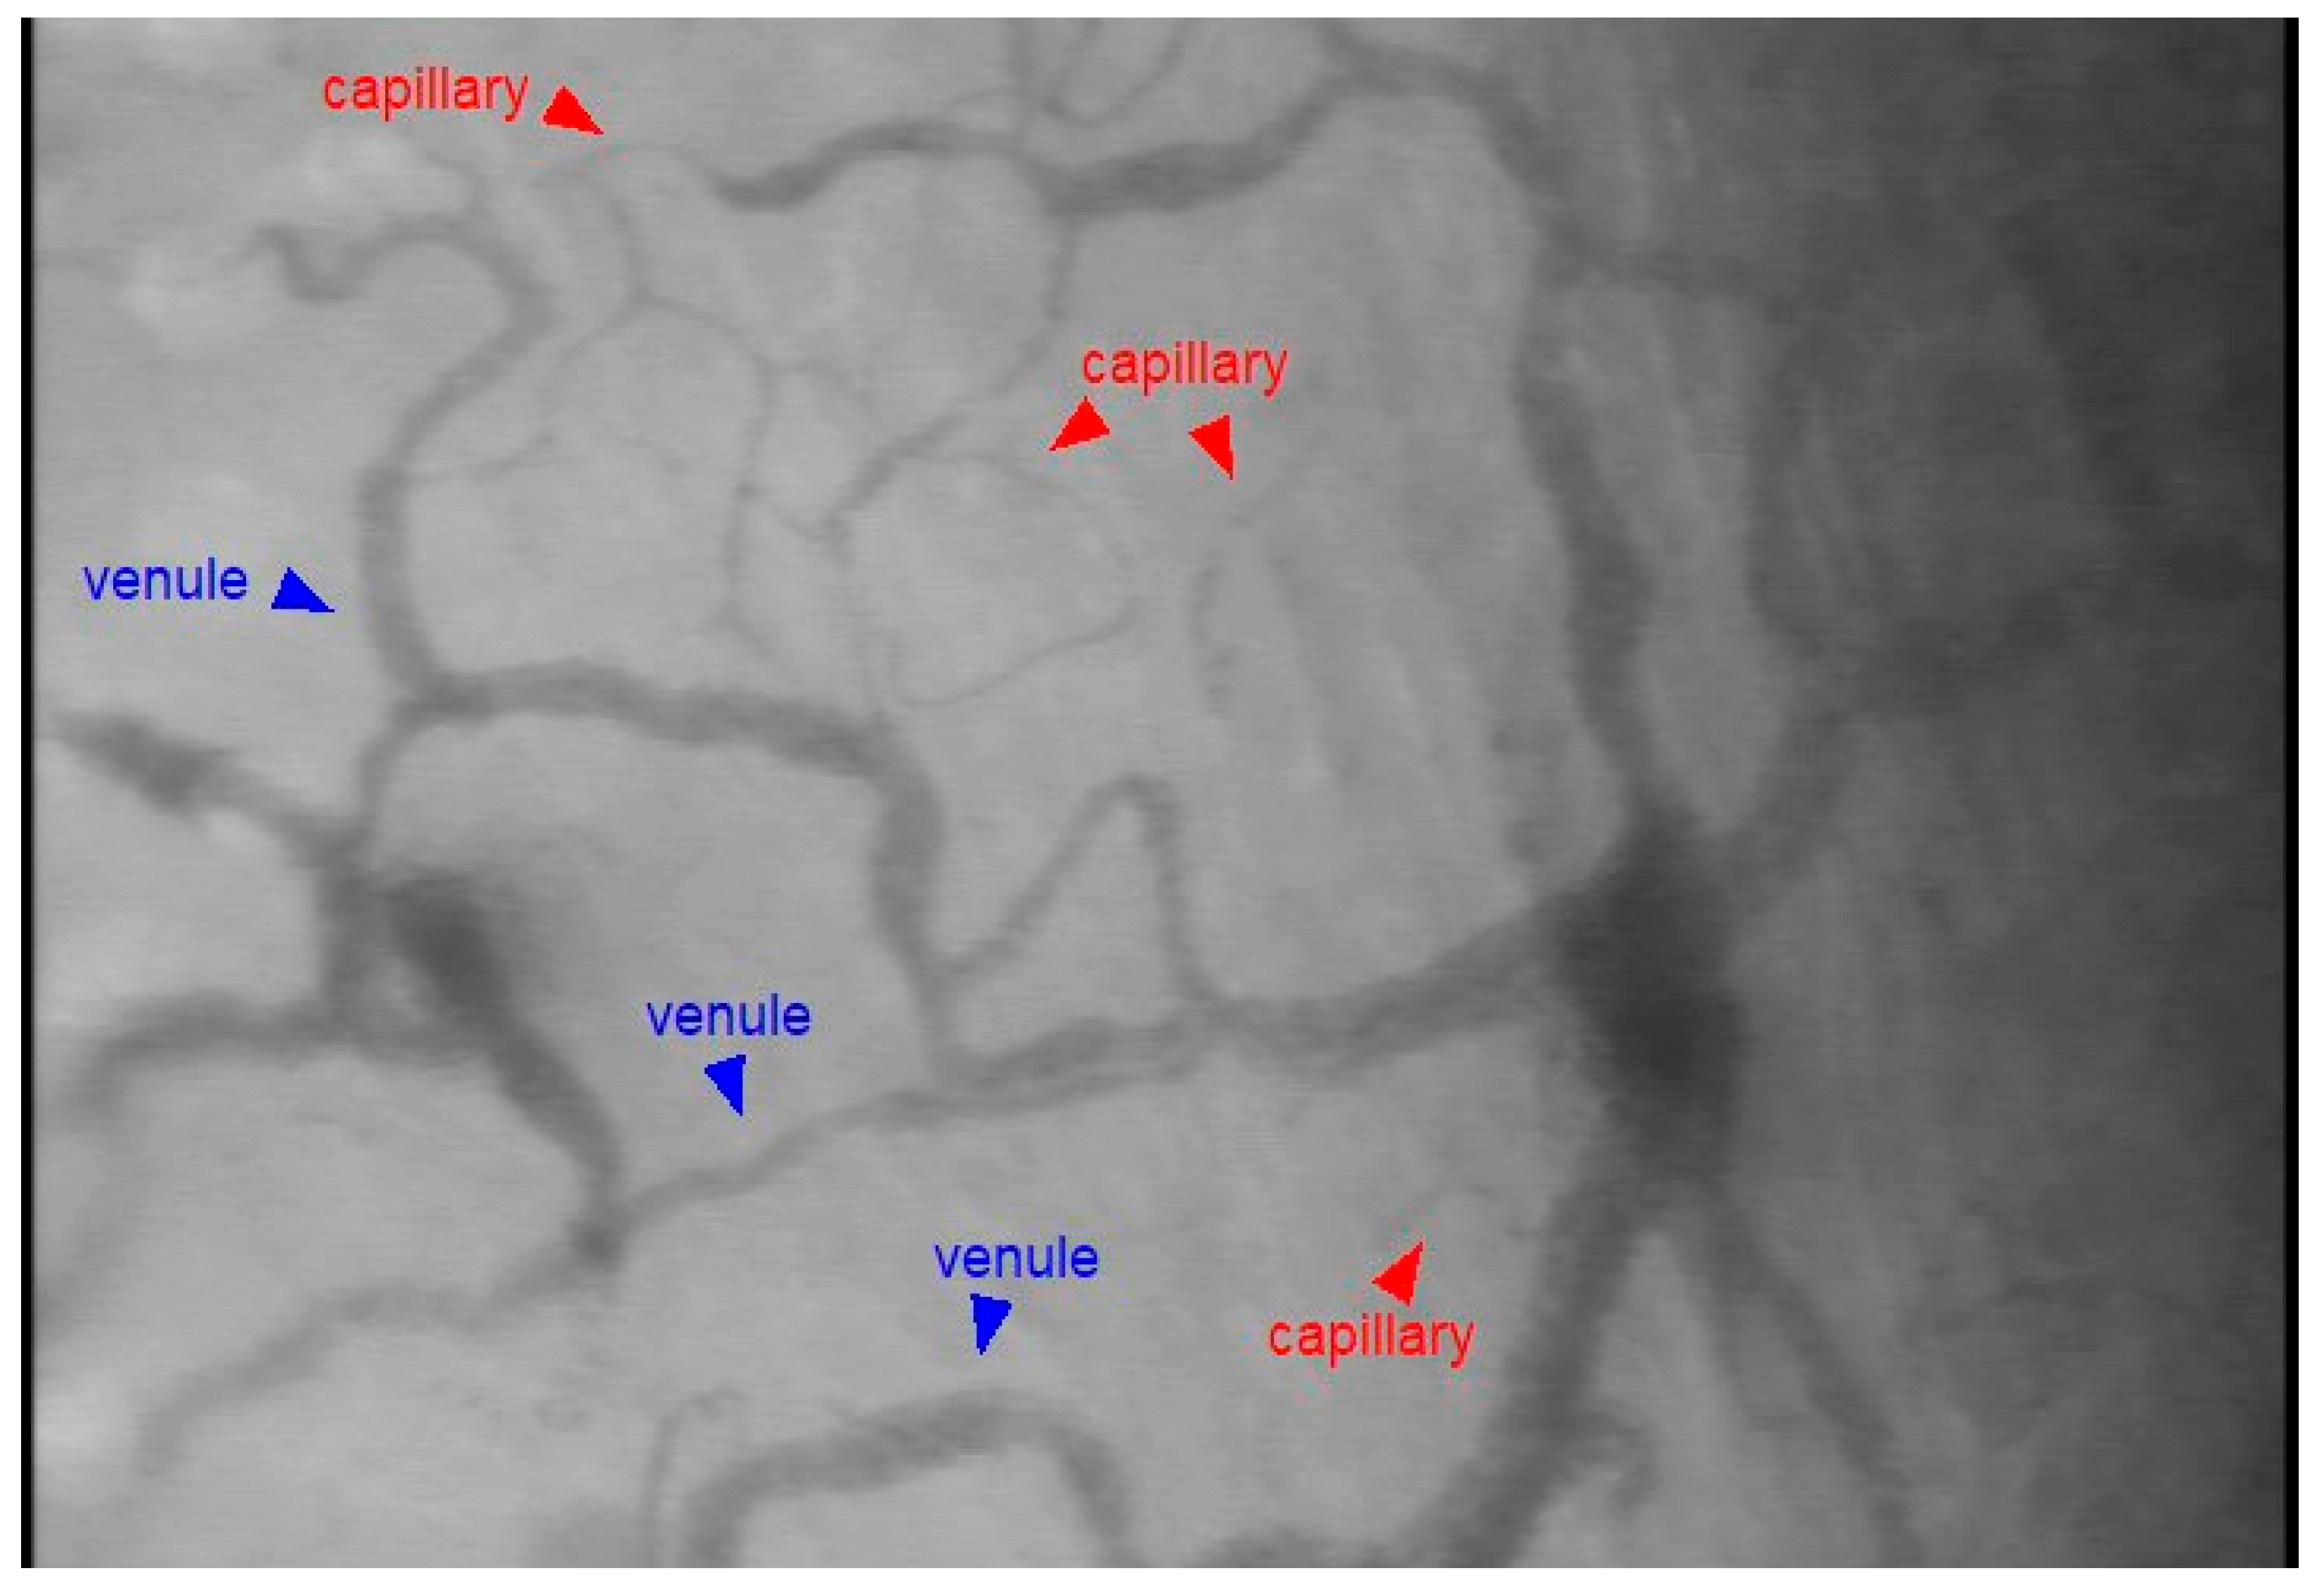

3.1. Microcirculatory Perfusion